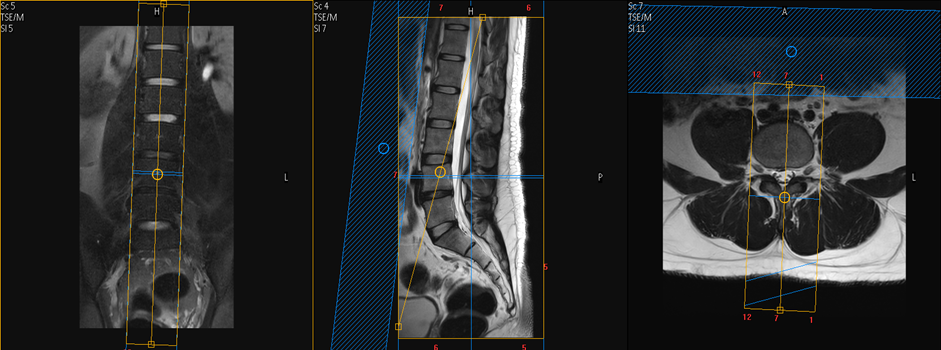

Lumbosacral spine

Position: Supine, give cushions under the legs

Centre the laser beam level of umbilicus or L4 vertebra.

Sequence: Sagittal T2, T1, Stir

Coronal: Stir / T2Fat sat

Transverse: T2W, T1W,3D if required.

Sagittal Plan

Sagittal plan on coronal or axial image using Block line parallel to spinal cord and check the position of block on another plane with appropriate angle.

Transverse Plan

Plan the transverse slice on sagittal or coronal image perpendicular to spinal cord or appropriate angle to inter vertebral disc.